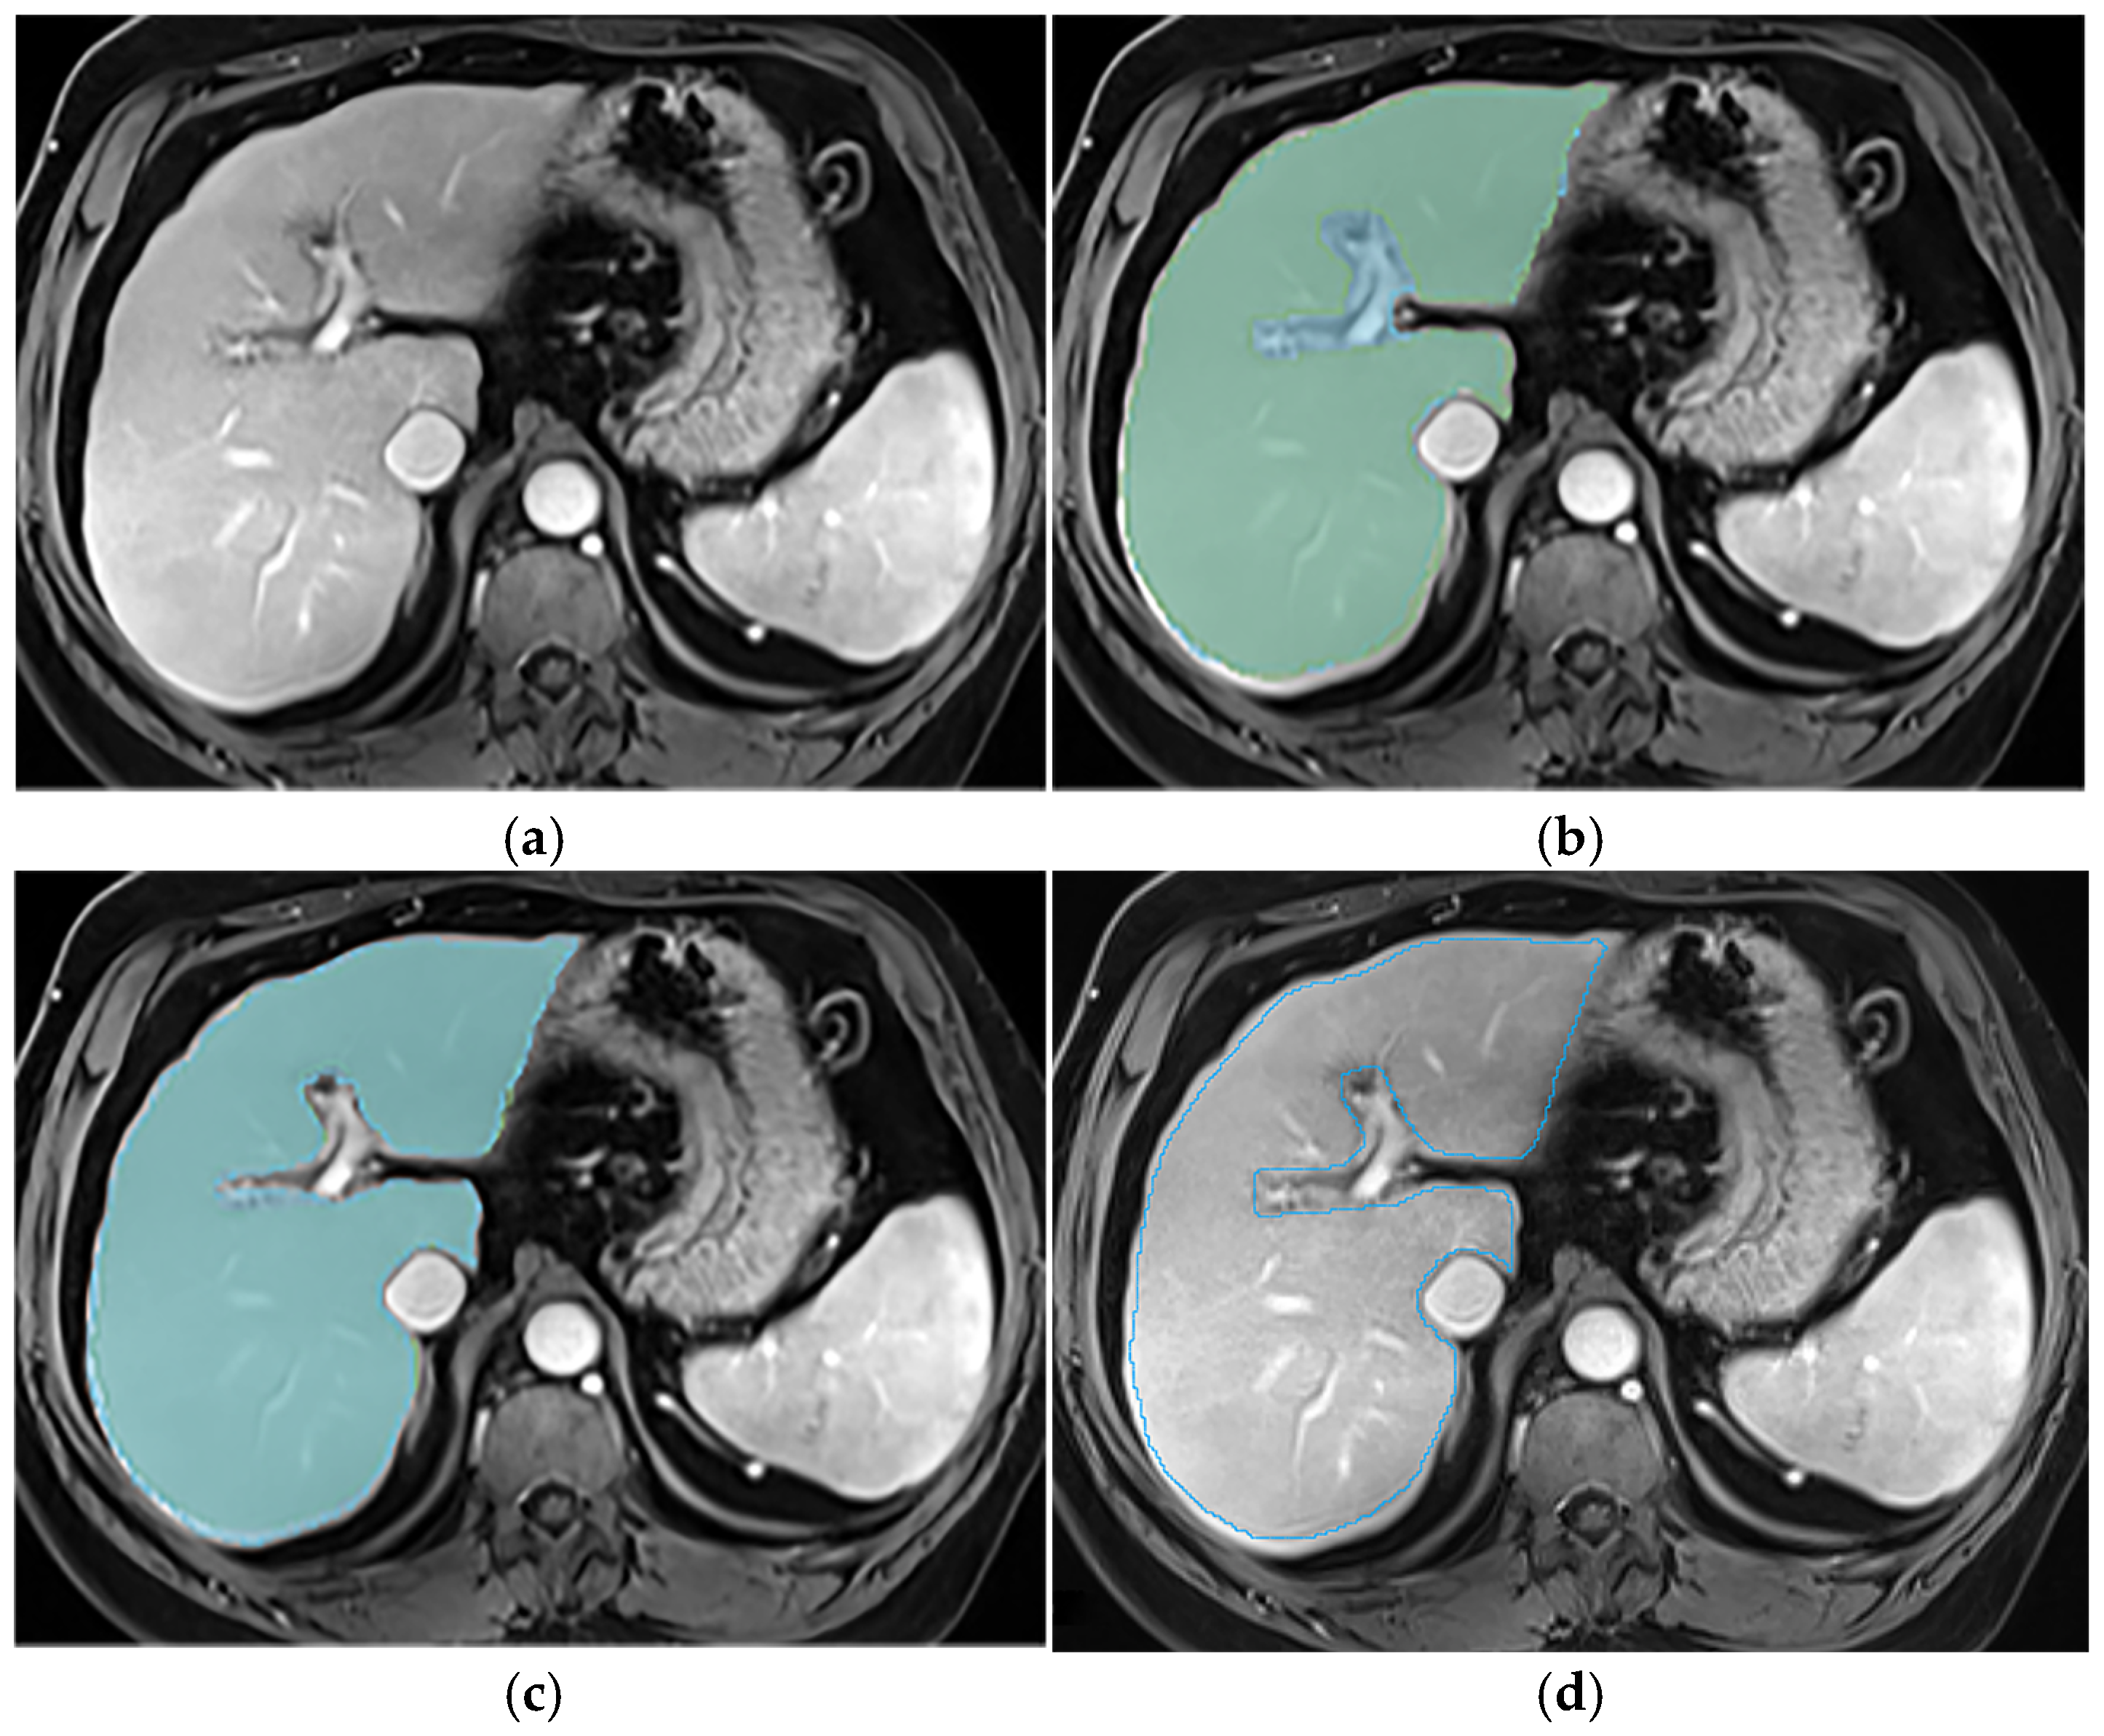

Appendix A.2. Hepatic Hilum Segmentation

Appendix A.3. Vascular Segmentation

Appendix A.4. Ligaments Segmentation

Appendix A.5. Multi-Part Liver Parenchyma